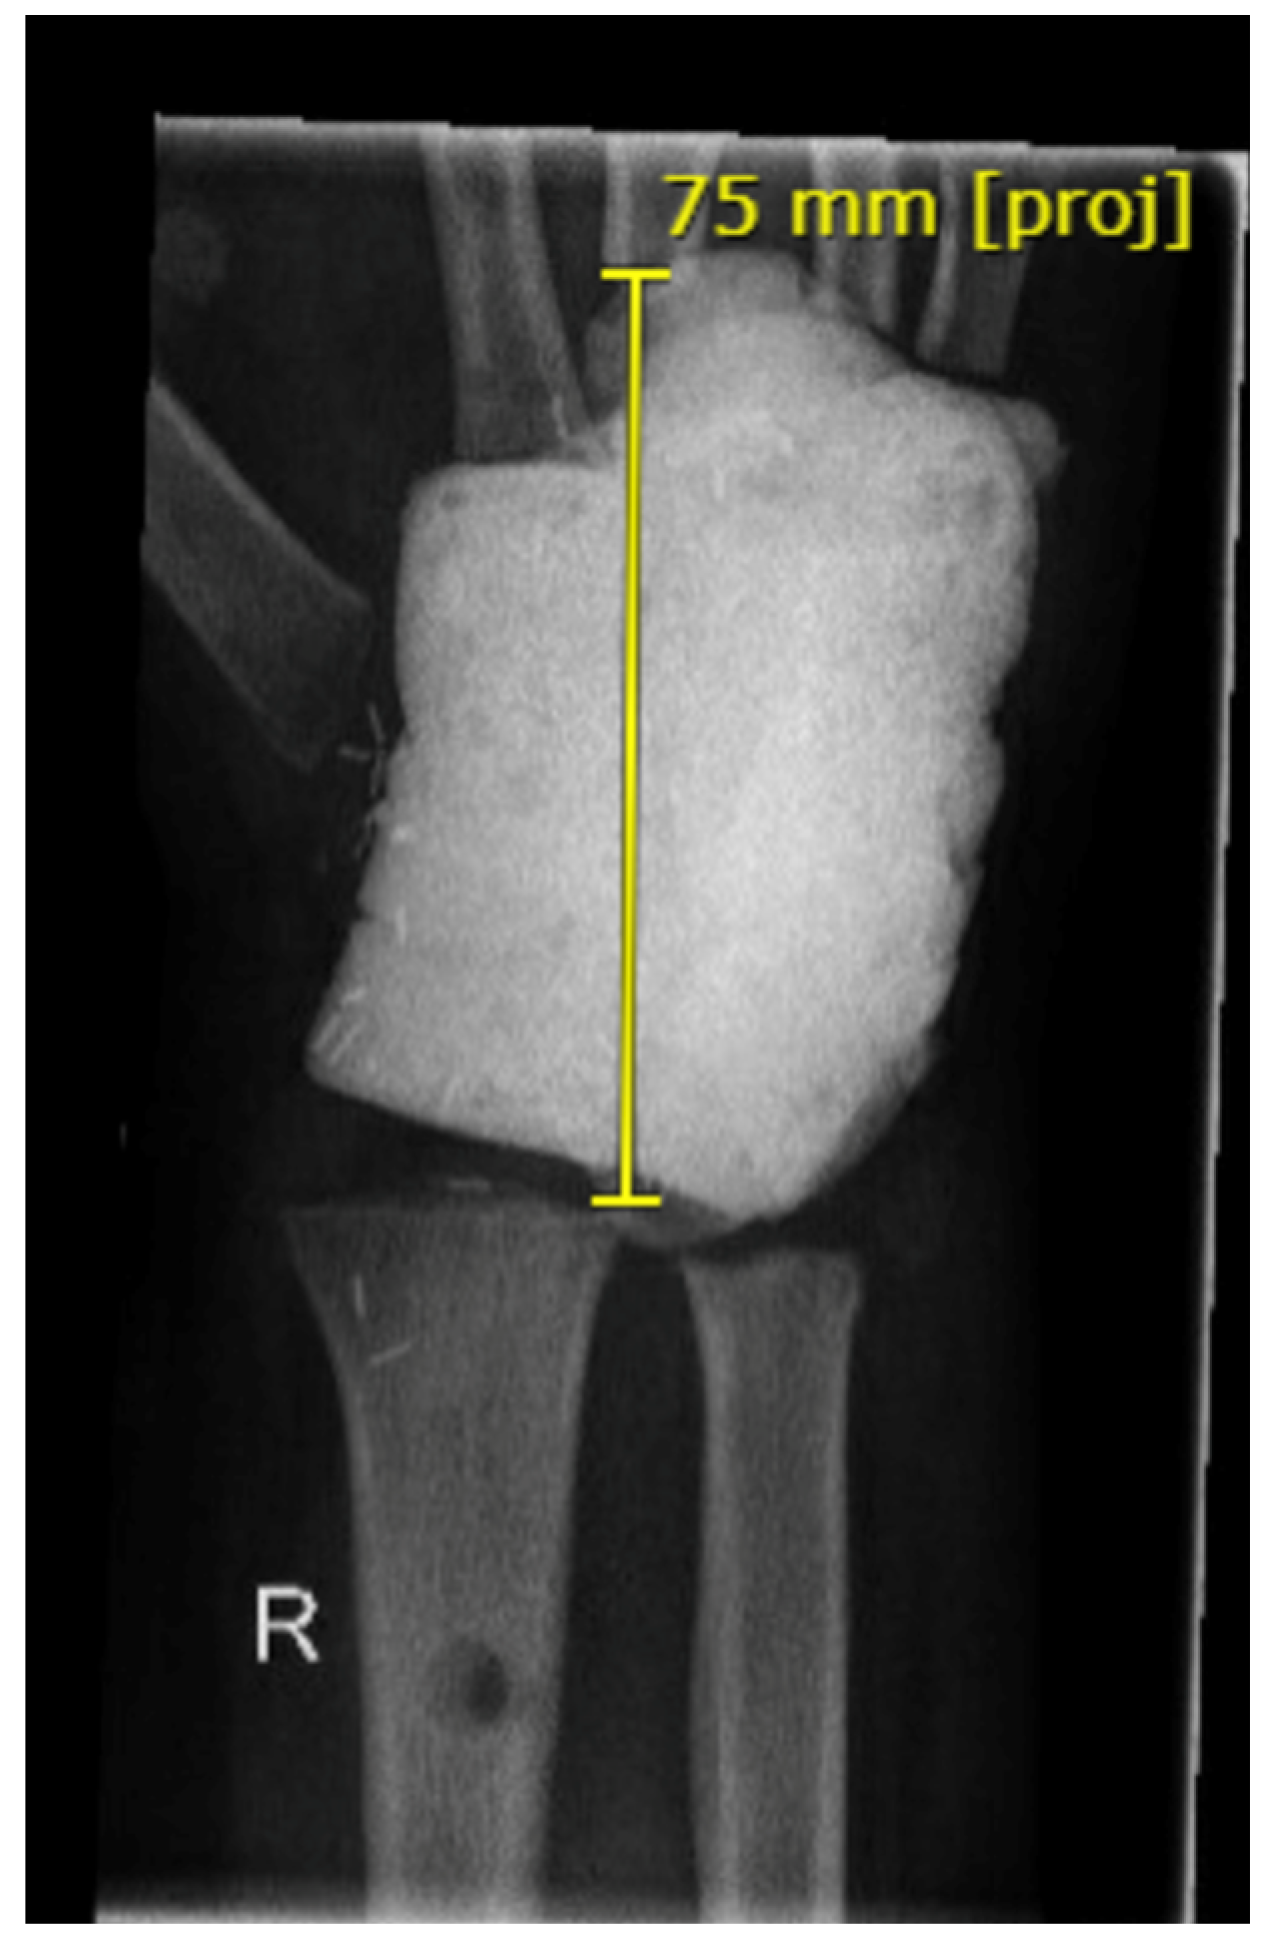

3.2.2. Arthrodesis of the Distal Radius and Middle Hand Using a Triangular-Shaped Vascularized Osteocutaneous Fibula Flap

| Case 3 | Complete wrist, distal radius and proximal metacarpals | Benign, aggressive bone tumor | 53 | 41 | 8 cm | Vascularized osteocutaneous triangular fibula | Wrist arthrodesis | N/A N/A | 0-0-0° 80-0-40° | 70% | MMWS = 45 DASH = 30 | yes | |